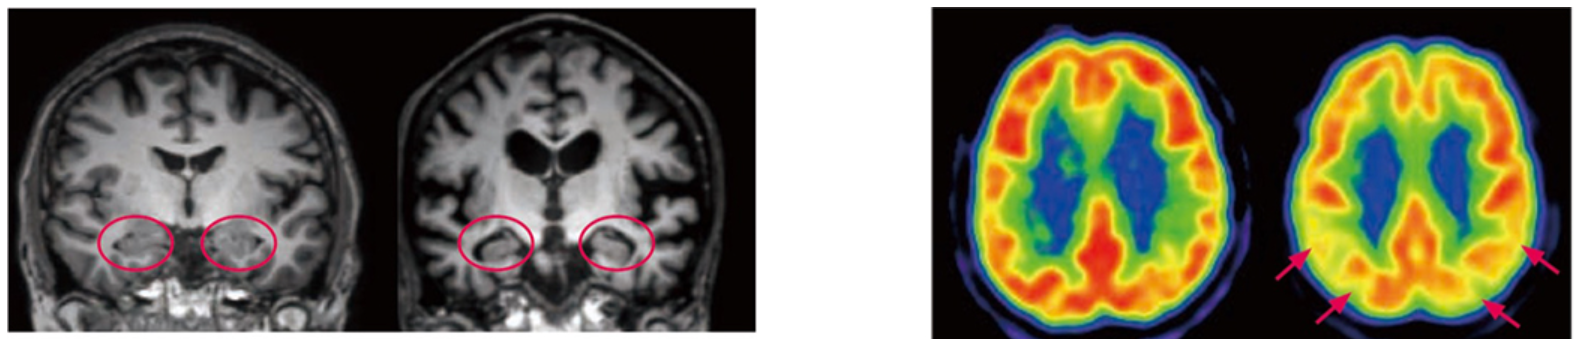

다음은 이미지 검사입니다. 우선 MRI(MRI를 할 수 없는 사람은 CT)로 뇌의 형태를 진단합니다. 알츠하이머병의 경우해마카이바그리고 그 주위가 강하게 위축되어 옵니다. 젊은 발병 알츠하이머 병의 경우 해마의 위축은 적고,정수리어서의 위축이 강합니다.

왼쪽 사진 : 정상자와 알츠하이머병의 MRI

정상자에서는 기억에 관계된 해마(○)의 위축은 없습니다만, 알츠하이머병에서는 위축이 보여집니다